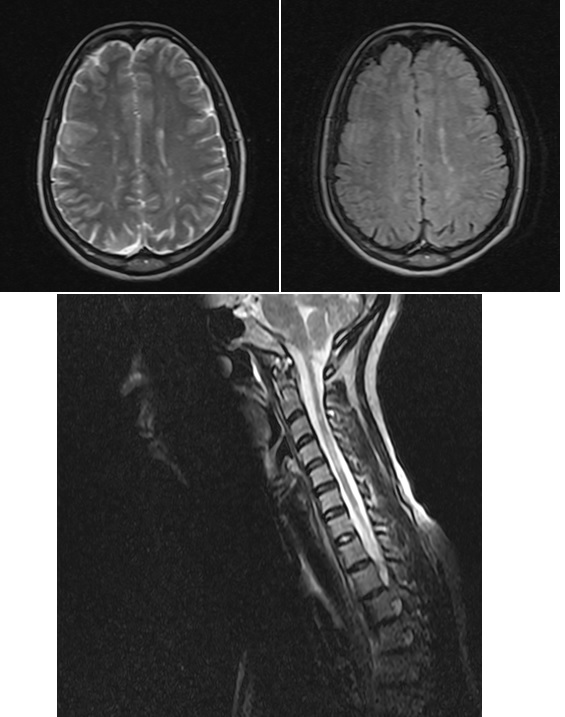

Figure 2: showing brain and spinal MRI of second patient.

figure 2